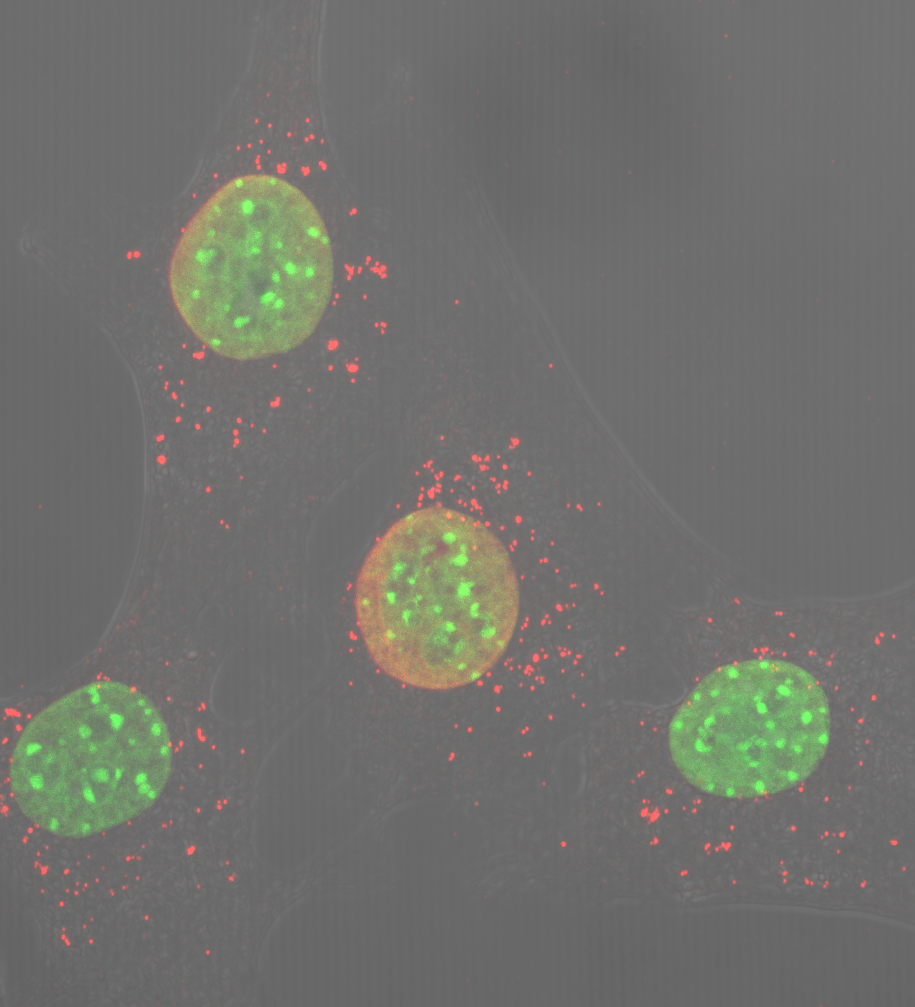

Opa1 is a mitochondrial fusion protein. It serves to fuse the internal membranes of mitochondria. Although present in all cells and tissues (except red blood cells), mitochondria are particularly abundant in muscle and liver, and their main function is to convert the energy in food into energy for cells. Mitochondria are highly dynamic; they join and separate, and grow and shrink constantly. These processes are known as mitochondrial dynamics.

Mitochondrial dynamics is one of the research lines addressed in Antonio Zorzano’s Complex Metabolic Diseases and Mitochondria Lab. To study this process, the scientists examine the proteins involved in mitochondrial membrane fusion, namely Mitofusin 1 and 2, and Opa1.

Authored by 24 researchers from various centres and involving a significant contribution by Aida Rodríguez-Nuevo, Angels Díaz-Ramos and Eduardo Noguera from Zorzano’s lab, this study focuses on the protein Opa1. To examine its functions, the researchers generated a mouse deficient in Opa1 only in skeletal muscle. "It was surprising to see how small they were and that they died after only a few months," explains Zorzano.

The article describes the animal phenotype and explains that the removal of Opa1 exclusively from skeletal muscle fibre triggers a severe inflammatory process that spreads from the muscle fibre throughout the body. The inflammatory response halts growth and shortens the lifespan of the animal. The scientists also describe the main molecular components of the cell signalling pathway that activates the inflammatory response in muscle.